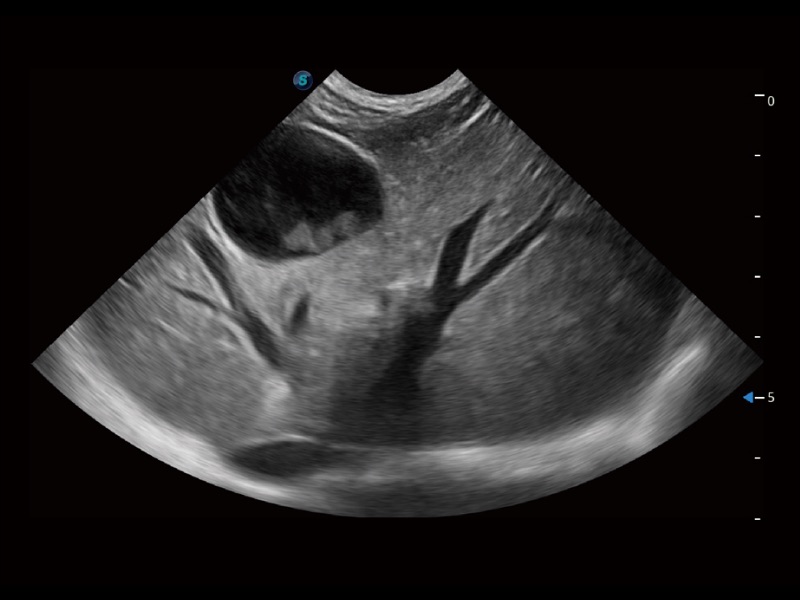

ProPet 70 进一步提升了微米成像算法,更加注重对基础原始图像的还原和保留,在有效减少斑点噪声、增强组织边界显示的同时,避免过度优化丟失真实的解剖信息。

大型犬、马科、农场动物及大型异宠动物

ProPet 70 全新的动物超声智能软件和丰富的探头群,为动物医生提供了高清晰度和精细分辨率的图像,无论在宠物、马科、畜牧还是实验室动物等应用中都可以轻松应对,为您的日常工作带来满意的体验。